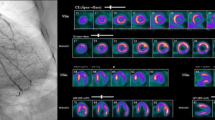

Our results confirm a positive relationship between the presence of functioning coronary collateral circulation and the amount of viable myocardium in patients with CTO. Figure 4 illustrates a case of insufficient collaterals with subsequent lower ejection fraction and a scar of > 75% of the anterior wall (Fig. 4). Figure 5 illustrates a case of well-developed left to right collaterals, a good ejection fraction and no fibrosis (Fig. 5).

Patient A: (upper left) angiography showing a proximal CTO LAD (black arrow) with very weak auto-collaterals (blue arrow) (Rentrop 0–1) which fill mainly ramus intermedius and not mid-distal LAD (Rentrop 0–1). There were no right to left collaterals to LAD; (on the right) SSFP 2CH image in systole a and diastole b with an ejection fraction of 30% as well as no thickening of the myocardium in the anterior wall; (bottom row) delayed enhancement images in short axis view (apical, mid-ventricular, basal slice) show a more than 75% extend of the scar in segments 7,13 and 14. The 2CH long axis confirms the thin anterior wall in the mid and apical segments (bottom right). Additional subendocardial scar after an LCX infarct, that was spontaneously recanalized (green arrow)

Patient B: (upper left) angiography showing a CTO RCA (black arrow) and (upper right); well-developed collaterals (Rentrop 3) from LAD to distal (PDA,PLV) and mid RCA (mid row left) SSFP images in systole and diastole (mid row right) with good ejection fraction (70%); (bottom row) delayed enhancement images in SA (apical, mid-ventricular, basal) and 2CH showing no fibrosis